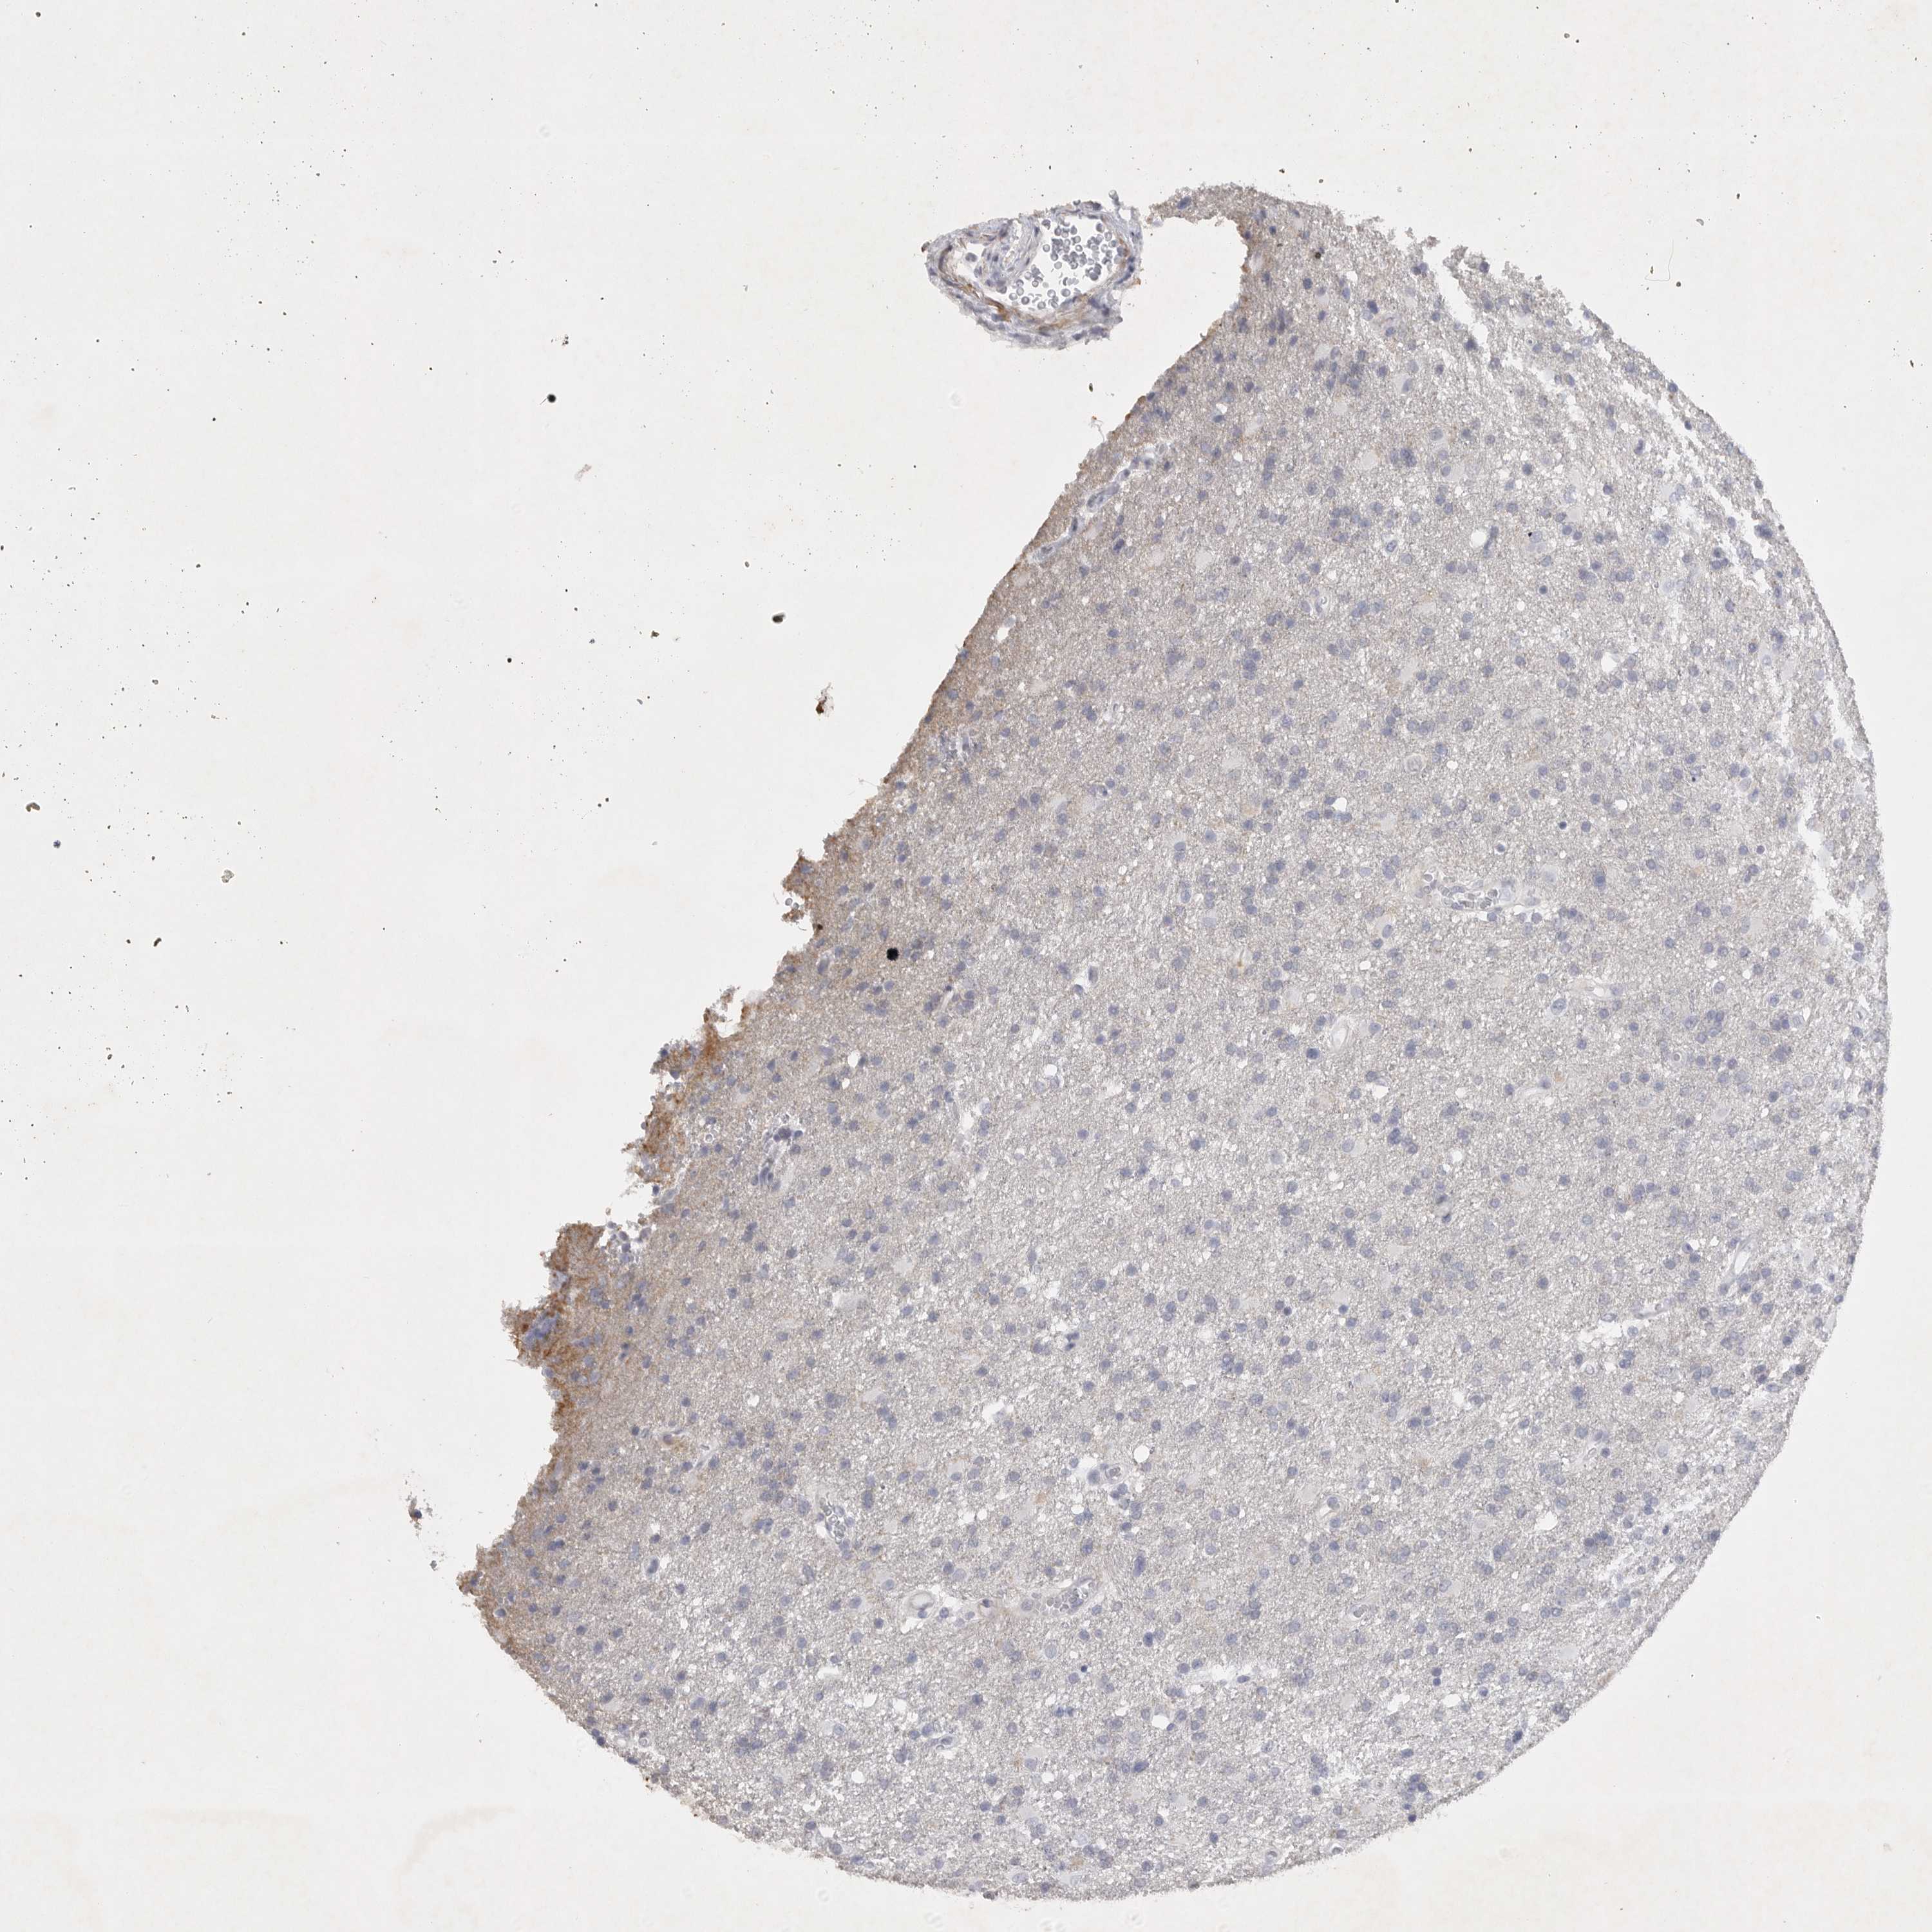

GLIOMA - Protein expressioni

A mouse-over function shows sample information and annotation data. Click on an image to view it in a full screen mode. Samples can be filtered based on level of antibody staining by selecting one or several of the following categories: high, medium, low and not detected. The assay and annotation is described here.

Note that samples used for immunohistochemistry by the Human Protein Atlas do not correspond to samples in the TCGA dataset.

Antibody stainingi

Antibody staining in the annotated cell types in the current human tissue is reported as not detected, low, medium, or high, based on conventional immunohistochemistry profiling in selected tissues. This score is based on the combination of the staining intensity and fraction of stained cells.

Each image is clickable and will lead to virtual microscopy that enables deeper exploration of all samples and also displays staining intensity scores, fraction scores and subcellular localization as well as patient and tissue information for each sample.

Antibody HPA027134

Antibody HPA027150

Antibody HPA029859

Antibody CAB022343

Staining

High

Medium

Low

Not detected

Intensity

Strong

Moderate

Weak

Negative

Quantity

>75%

75%-25%

<25%

None

Location

Nuclear

Cytoplasmic/membranous

Cytoplasmic/membranous,nuclear

Glioma, malignant, High grade

Glioma, malignant, Low grade

Glioblastoma, NOS